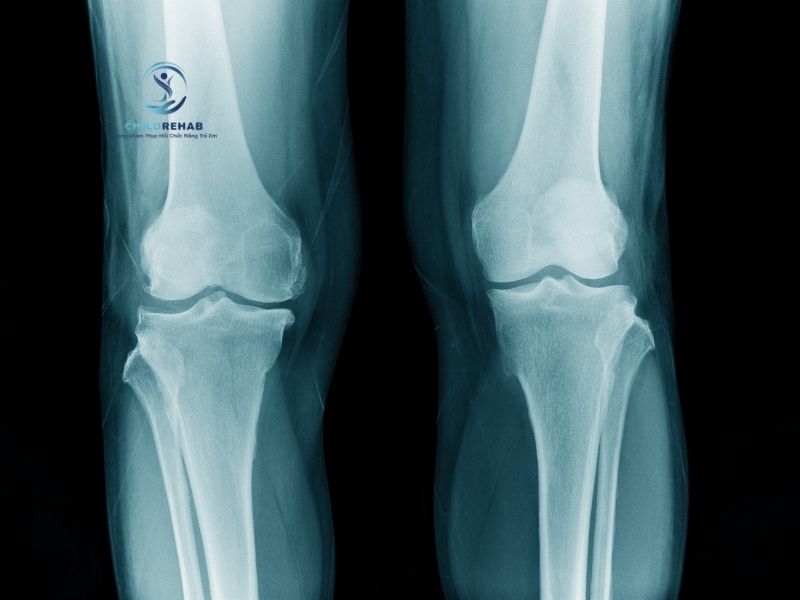

Trong quá trình phát triển thể chất, nhiều trẻ nhỏ có thể xuất hiện tình trạng chân chữ X ở trẻ – khi hai đầu gối chạm vào nhau nhưng hai mắt cá chân lại cách xa khi đứng thẳng. Đây là hiện tượng khá phổ biến, đặc biệt ở giai đoạn từ 2–5 tuổi và thường được xem là sinh lý bình thường. Tuy nhiên, khi tình trạng này kéo dài hoặc có dấu hiệu bất thường, phụ huynh thường băn khoăn: Trẻ bị chân chữ x có cần chụp x-quang không?

Thực tế, không phải mọi trường hợp chân chữ X ở trẻ đều cần đến chụp X-quang. Trong nhiều trường hợp nhẹ, bác sĩ có thể đánh giá thông qua quan sát lâm sàng và theo dõi sự phát triển theo thời gian. Tuy nhiên, khi có những dấu hiệu nghi ngờ bất thường về cấu trúc xương hoặc trục chân, việc chụp X-quang có thể được chỉ định để hỗ trợ chẩn đoán chính xác hơn. Điều quan trọng là phụ huynh cần hiểu rõ khi nào việc chụp X-quang là cần thiết và khi nào có thể chỉ cần theo dõi.

Việc hiểu đúng trẻ bị chân chữ x có cần chụp x-quang không? sẽ giúp phụ huynh tránh được hai tình huống phổ biến: một là lo lắng quá mức dẫn đến yêu cầu chụp không cần thiết, hai là chủ quan không thực hiện khi thực sự cần thiết. Bởi lẽ, X-quang là một công cụ hỗ trợ chẩn đoán hữu ích nhưng cần được sử dụng đúng chỉ định để đảm bảo an toàn và hiệu quả cho trẻ.